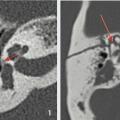

Concerne surtout l’enclume (ou incus), mais aussi le marteau (ou malleus) et l’étrier (ou stapes).

Surdité persistant à distance du traumatisme (après réparation de la membrane tympanique et résorption de l’hémotympan). Le scanner peut montrer une lésion au niveau des osselets : luxation incudo-stapédienne ou incudo-malléaire (fig. 2), dislocation de l’enclume ou fracture ossiculaire, par ordre de fréquence.